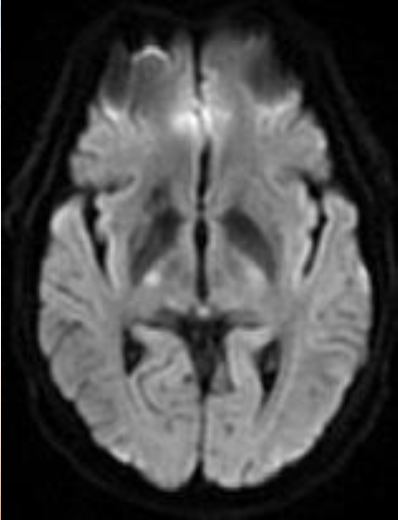

颅脑DWI

病历夹什么径技·第152期|串联营病历夹:川陕大营_https://www.jmylbn.com_新闻资讯_第40张

病历夹什么径技·第152期|串联营病历夹:川陕大营_https://www.jmylbn.com_新闻资讯_第41张

<<滑动查看下一张图片>>

诊断:右侧放射冠区急性脑梗死。